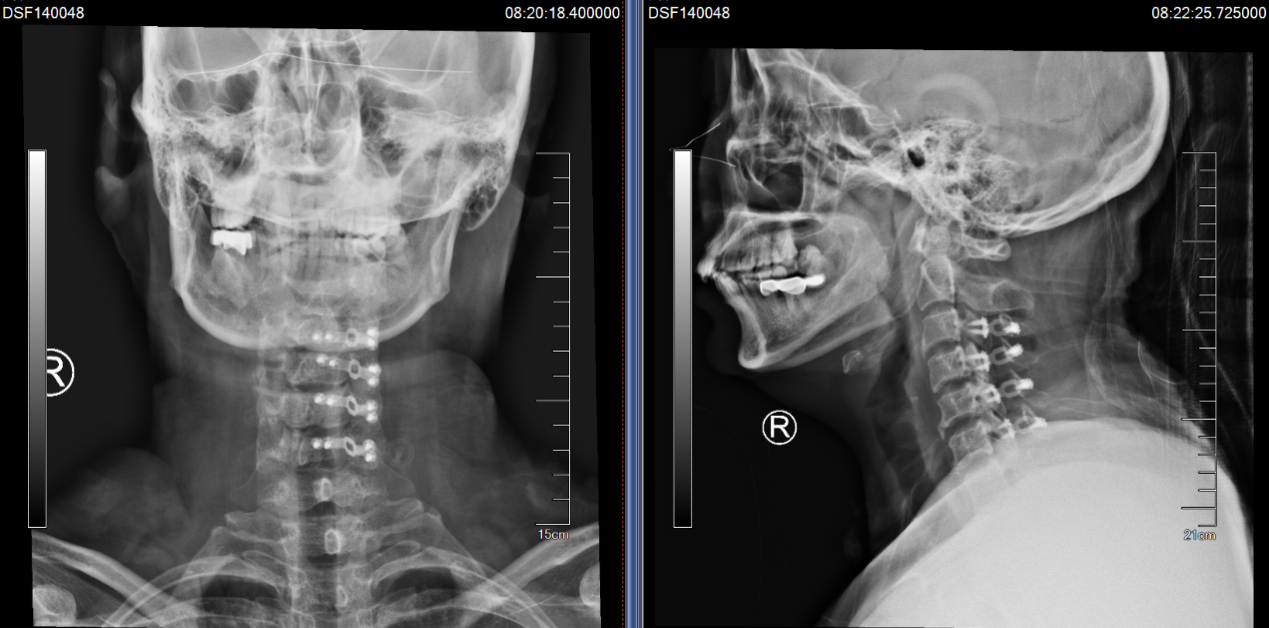

意识到问题的严重,沈阿姨要求尽快手术治疗,于是在入院后的第二天,姜主任为她进行了颈椎前路椎间盘切除+椎间融合术(ACDF术)。手术起到了“精准减压”的效果,通过颈部一个3cm左右的横行小切口,准确到达病灶所在位置,解除神经根压迫,术后她颈肩痛的症状立刻得到了缓解,可谓“术到病除”。

(颈椎CT提示患者C4-5的椎间盘突出(右后方),椎间隙后缘骨赘增生)

在沈阿姨术后第三天,其表姐王阿姨也在她的推荐下来住院了。王阿姨的症状和沈阿姨几乎一样,在住院的前1个月,她右上肢的疼痛感突然加剧,病变的节段是C5-6,看到表妹的手术效果如此显著,她决定也来做手术。

(C5-6 ACDF术,患者手术疗效确切)